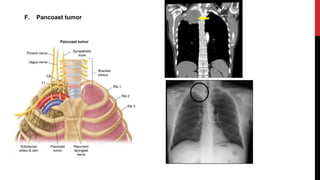

F. Pancoast tumor